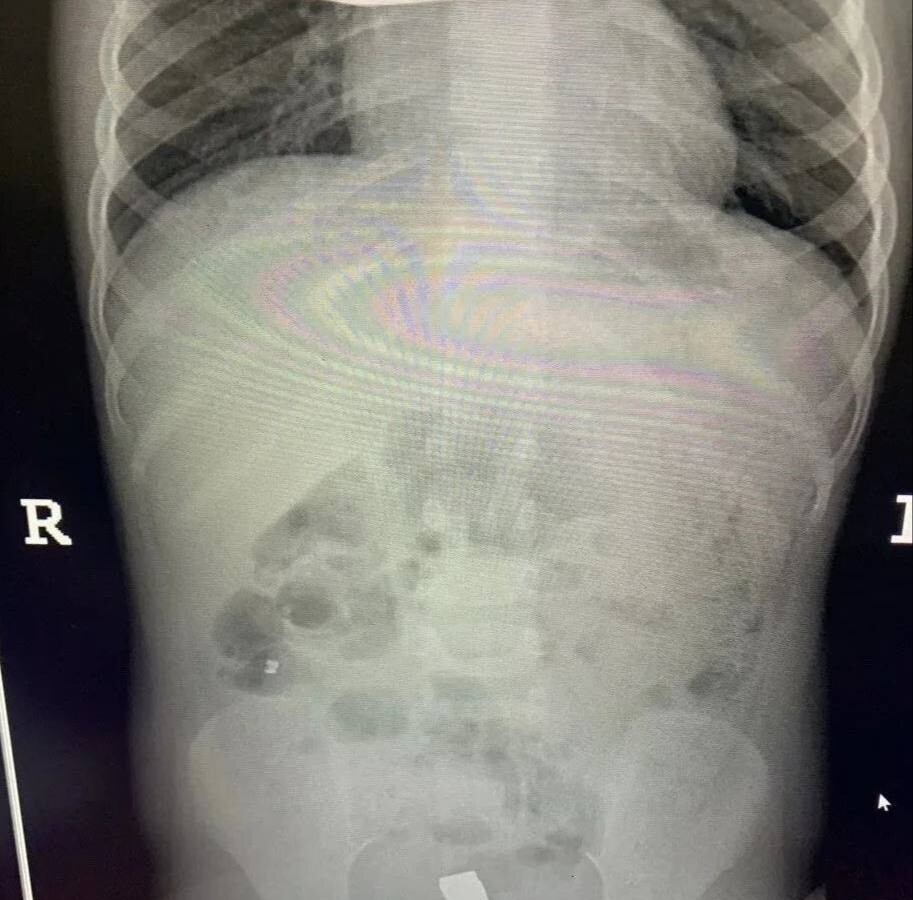

Инцидент произошел в Балашихе — малолетнюю пациентку с жалобами на острую боль в животе доставила в больницу бригада скорой помощи. Обследование показало, что внутри у ребенка большое количество металлических инородных тел. Девочку немедленно отправили на операционный стол.

Врачи приняли решение обойтись без полостного вмешательства. Через крошечные проколы специалисты аккуратно извлекли 20 магнитов из организма ребенка — они успели притянуться друг к другу и прожечь стенку кишки насквозь. Пять штук и вовсе мигрировали в область малого таза.

Хирурги зашили ребенку перфорированный кишечник. Девочка быстро оправилась и уже выписана домой.